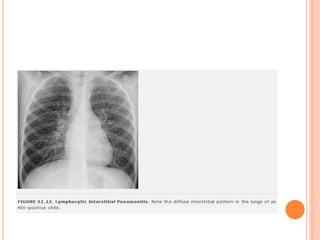

PADRÕES PERIBRÔNQUICOS E INTERSTICIAIS:

OPACIDADES NEBULOSAS, RETICULARES E

RETICULONODULARES

 Doenças intersticiais

 Causa mais comum: infecção viral ou por

Mycoplasma